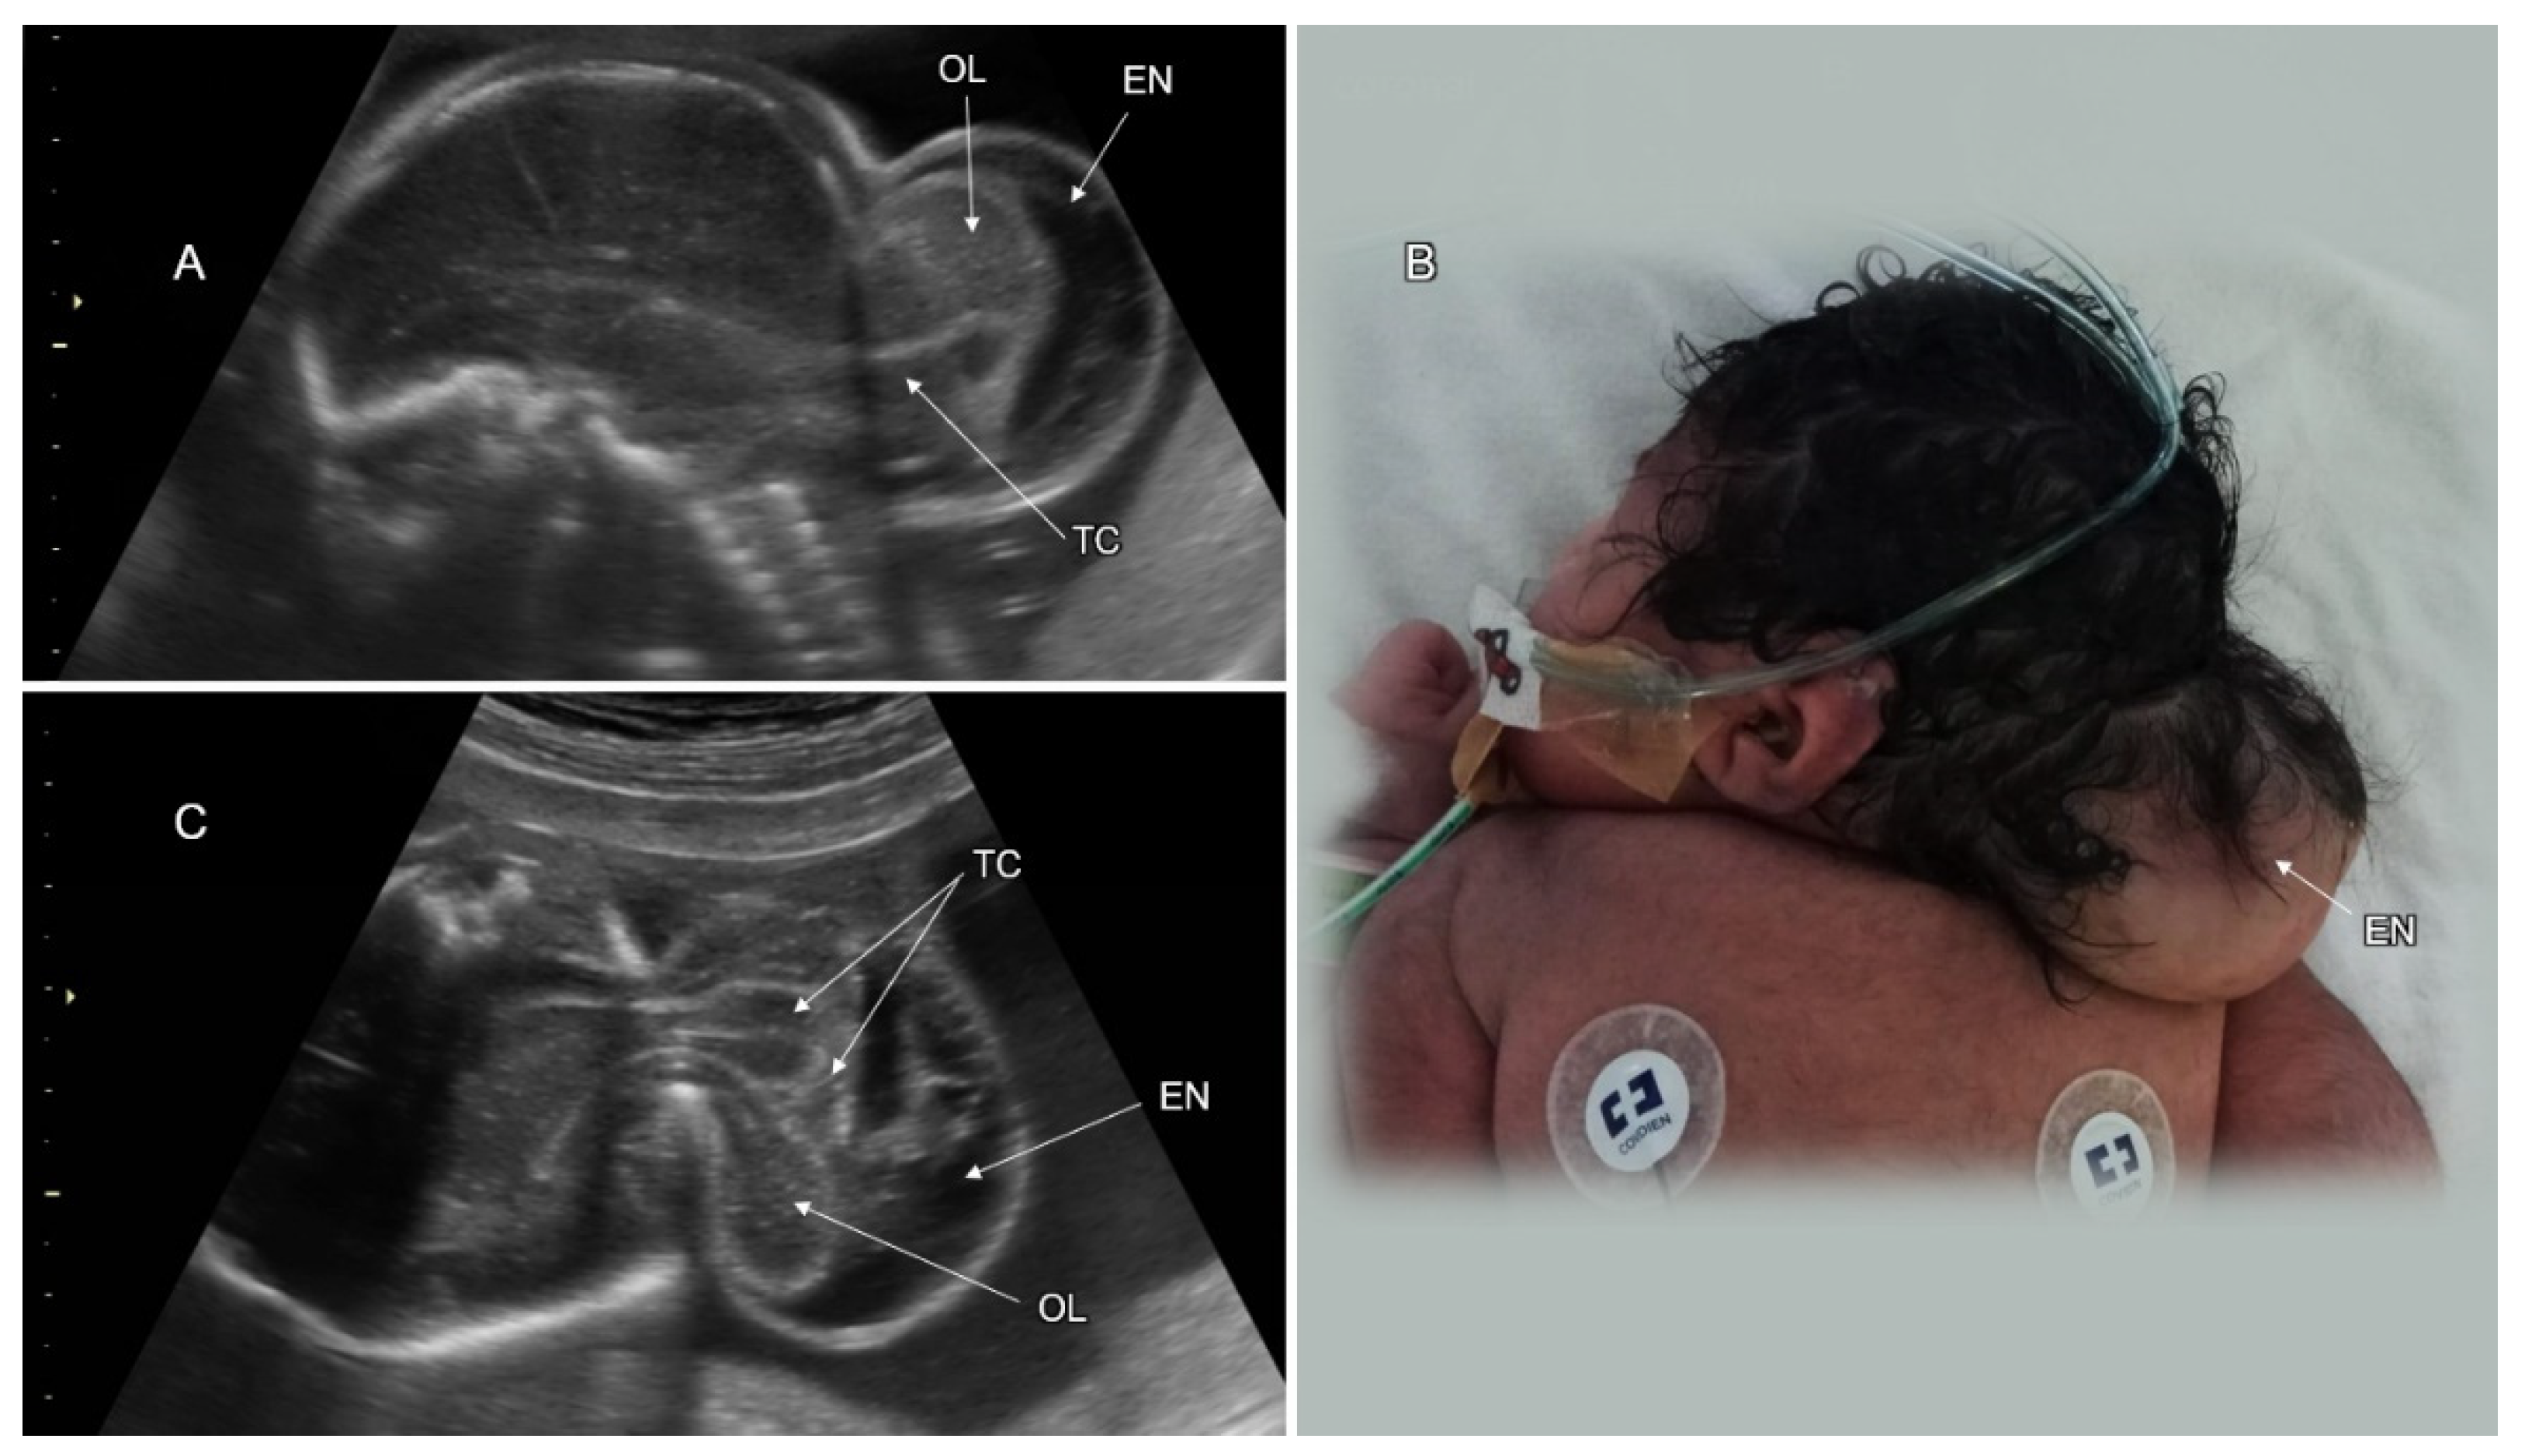

3.2. Spinal Dysraphism